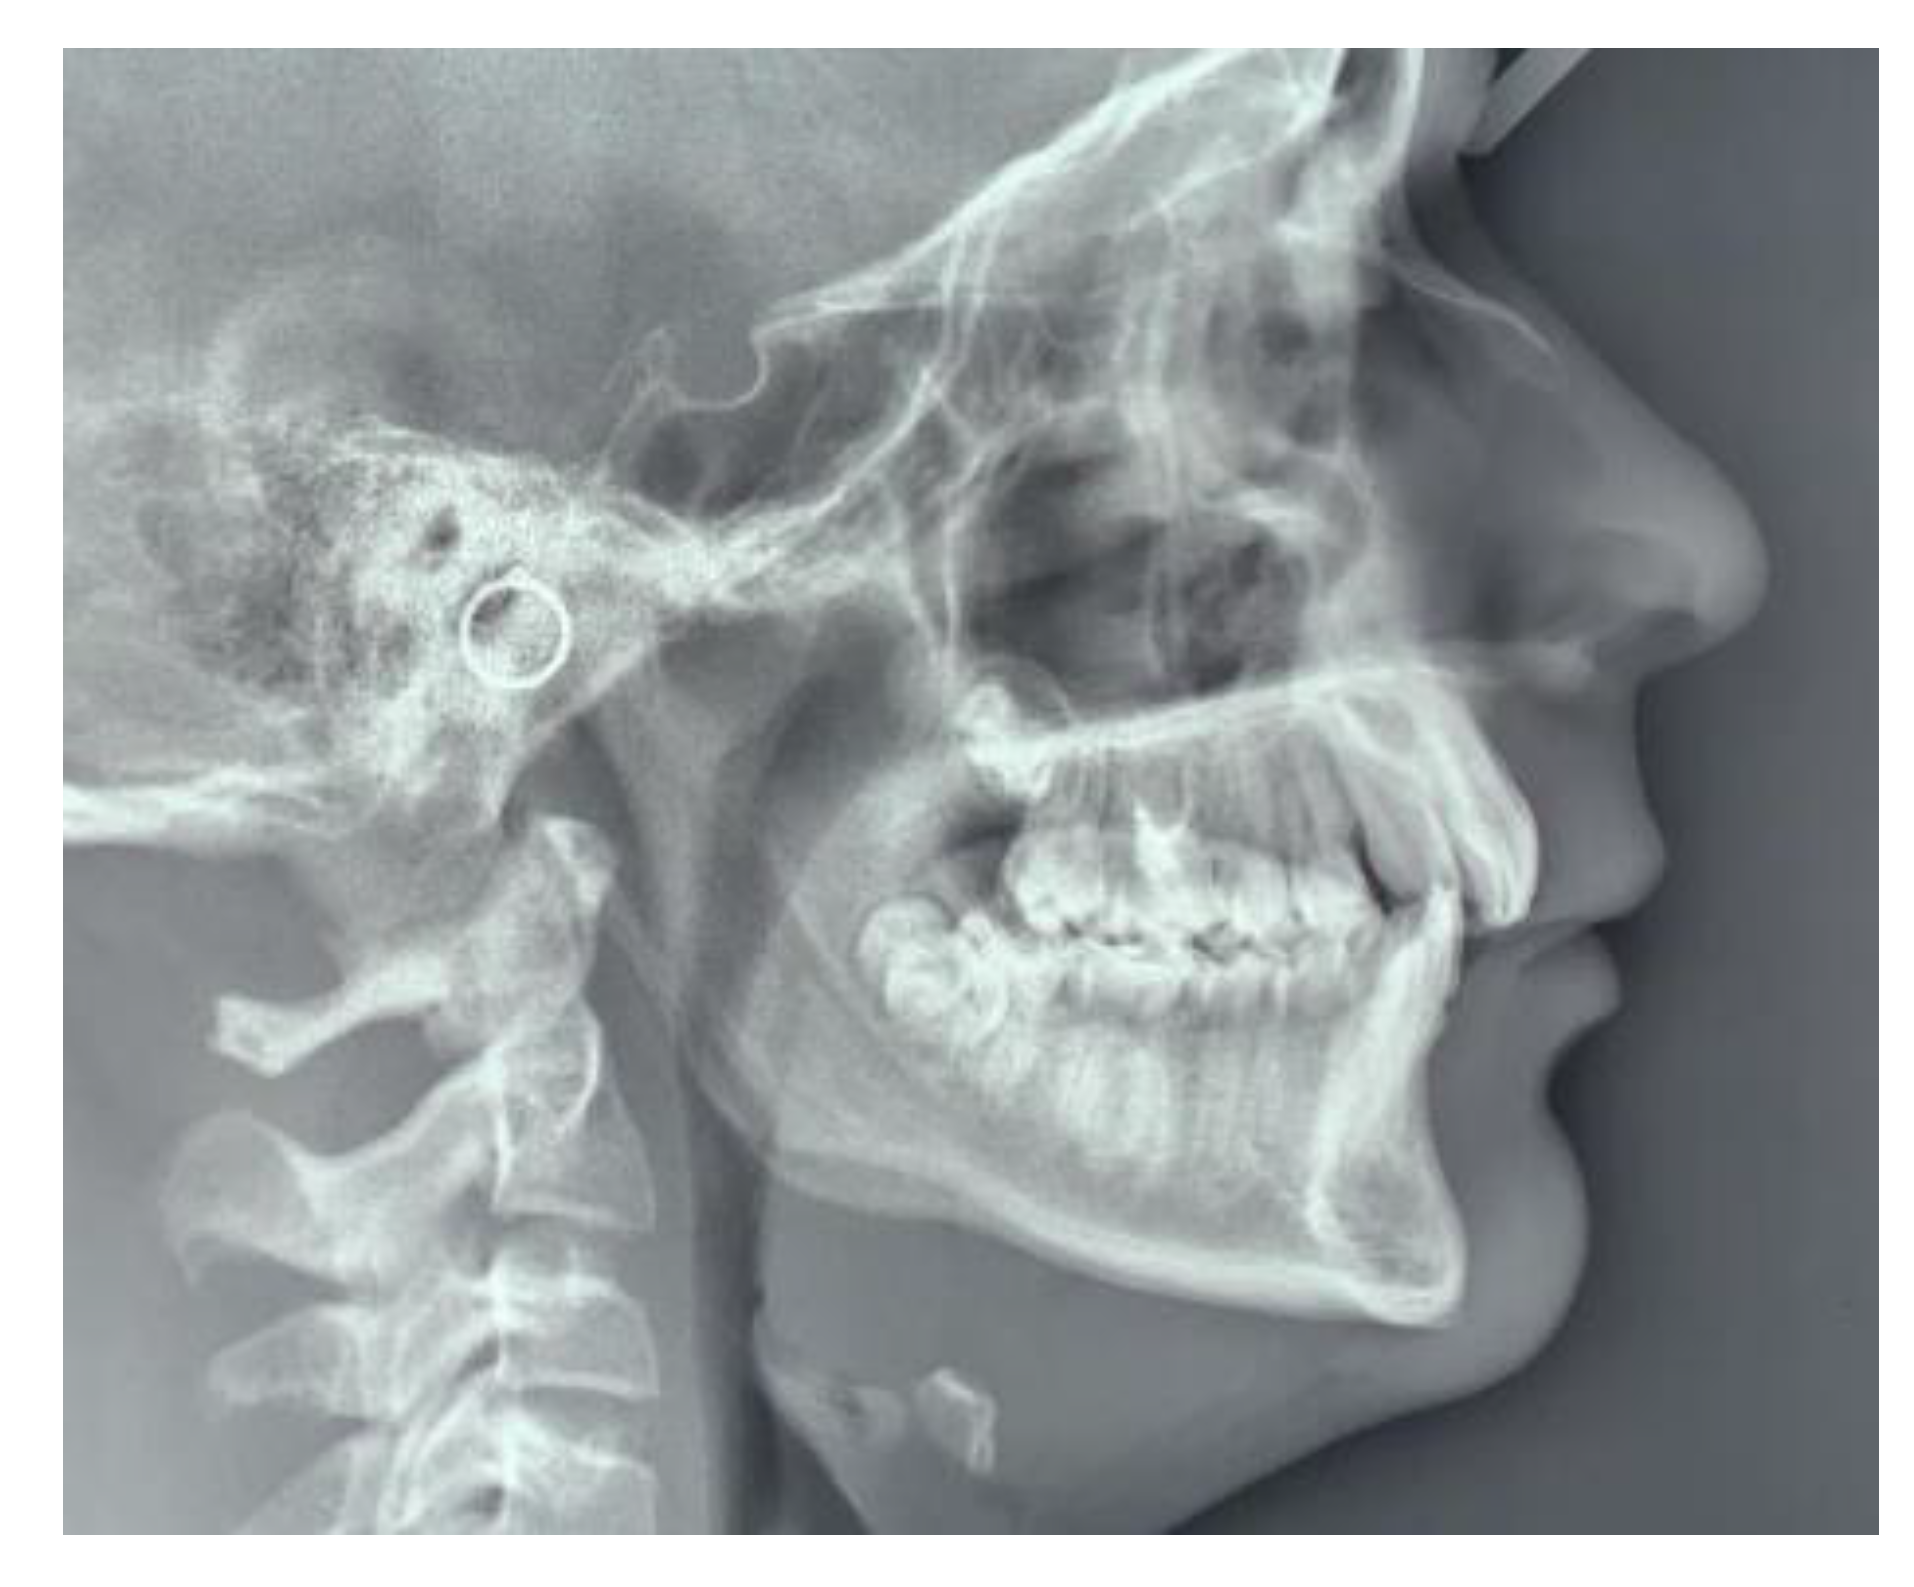

The sella turcica and pterygopalatine fissure morphologies were analysed by evaluating the measurements according to the criteria by Axelsson et al. [16]: the width/length was considered as the measurement from the tip of the dorsum and the tuberculum while the height/depth of sella and pterygopalatine fissure was a perpendicular line to w-line to the deepest point on the floor of the sella or pterygopalatine fissure. The ratio between h-line and w-line of both anatomical parts was measured (Figure 4).

A higher percentage of APAD was found in the test group and the difference between test and control group was statistically significant both with univariate analysis (chi-square test, p < 0.05) and multivariate analysis. A significant difference (Wilcoxon rank-sum (Mann–Whitney) test, p < 0.05) between the two groups was also recorded for the shape of pterygopalatine fissure (the fissure in patients with MCI was elongated than in patients who do not have dental abnormalities) while the difference for the shape of sella turcica was not significant (Wilcoxon rank-sum (Mann–Whitney) test, p > 0.05) (Table 4).

Moreover, in this study, we found a decreased width of the pterygopalatine fissure. Nevertheless, in previous studies, it was observed that in patients with an abnormal direction of maxillary canines eruption, the vertical height and sagittal length of the maxilla were reduced [23]. A decreased sagittal width of the pterygopalatine fissure may be caused by a deviated maxillary growth which in turn is linked to a deviated skeletal cranial growth while, on average, the space available for the eruption of the maxillary canines seemed sufficient to suggest a non-existent cause of mechanical obstacle to the physiological eruption. The relationship between skeletal anomalies and MCI may be linked to the activation of neural crest cells and homeobox genes during growth [1]. Neural crest cells undergo a transition from ectoderm to mesenchyme due to some biological signals such as bone morphogenetic protein BMP2 and BMP4, as they migrate to the pharyngeal arches to form the bones of the face, and are necessary for the formation of odontoblasts, dental pulp and periodontium; furthermore, paired box genes PAX9 mutations have been reported to be associated with dental agenesis [7]. Indeed, their expression is important to direct the tooth eruption but also to mediate the interaction between notochord and sclerotomes [8], from which the vertebrae are formed, and this could explain the association with the deficit of the posterior arch of C1.

Figure 4. Sella Turcica (a) and pterygopalatine fissure morphology analysis (b). Reference lines: h-line (height/depth) and w-line (width/length).